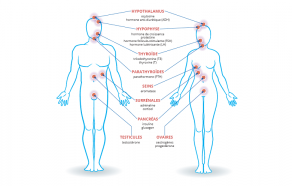

Le système endocrinien est l'ensemble des glandes (dites « endocrines ») qui libèrent des hormones dans le sang : ovaires chez les femmes, testicules chez les hommes et pour tous, thyroïde et parathyroïdes, hypophyse, hypothalamus, pancréas (ilôts), glandes surrénales [...]